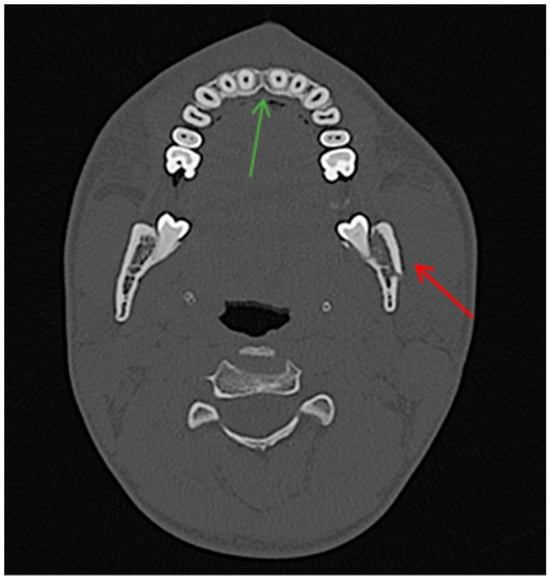

Diagnostic Utility of the “Air Sign” as a Radiological Indicator for Mandibular Body and Angle Fractures

- Gontarz, M.; Bargiel, J.; Gąsiorowski, K.; Marecik, T.; Szczurowski, P.; Zapała, J.; Wyszyńska-Pawelec, G. “Air Sign” in Misdiagnosed Mandibular Fractures Based on CT and CBCT Evaluation. Diagnostics 2024, 14, 362. [Google Scholar] [CrossRef]